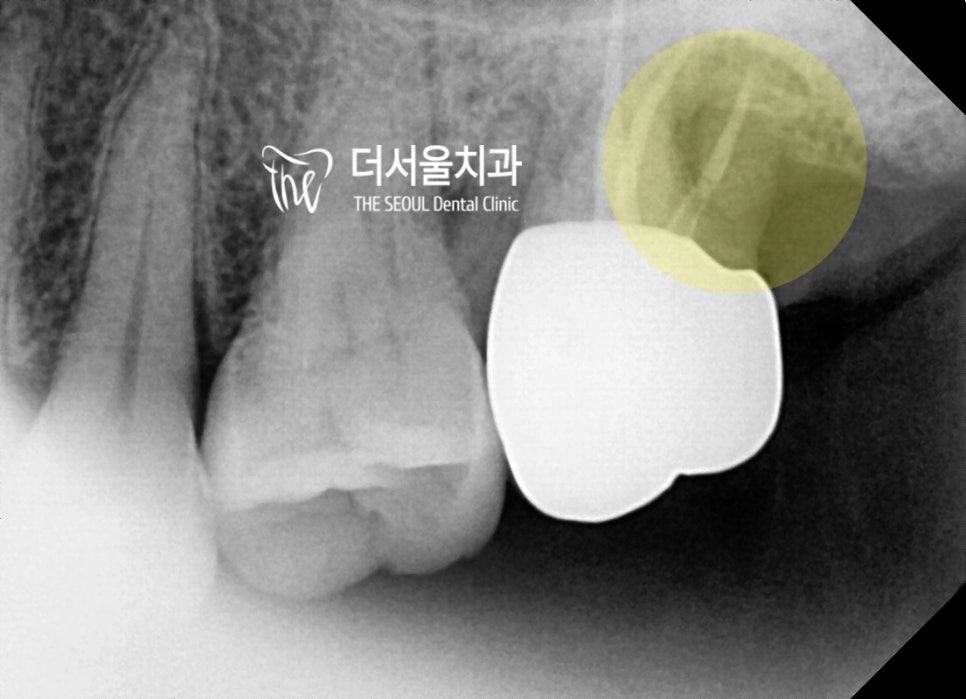

엑스레이를 찍어서 살펴보면,

원인을 바로 알 수 있었습니다.

#27번 구치의 distal plane 쪽에

bone defect 이 일어나 있습니다.

과거 신경치료 및 보철치료까지

받으셨던 곳인데 염증 재발 및

관리 소홀이 주요 원인으로 생각됩니다.

뼈가 거의 다 녹아서, 치근이 밖으로

다 드러나와있는 상황입니다.

게다가 손으로 만졌을 때도,

동요도(mobility)가 느껴졌기 때문에

이 치아는, 보존이 불가능합니다.